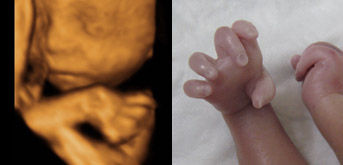

手畸形(鹰爪)

手裂由于我们现在生存的环境不断恶化,自然环境中雾霾、噪声、水源污染、饮食污染等,加上社会节奏加快,人们价值取向的变化,人们的心理压力增加,使得原本简单的人类世代繁衍,变得极其复杂,因此就造成我们还没有出生的胎儿在发育过程中出现种种障碍,造成胎儿停止发育、流产、胎儿畸形、胎死宫内等等。因此为了提高出生人口的质量,减少残疾儿的出生,《中华人民共和国母婴保健法》提出进行产前诊断与产前筛查。顾名思义是指对胎儿进行先天性缺陷和遗传性疾病的诊断,产前筛查是为诊断提供咨询、检查的方式。